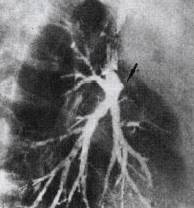

“支气管截断征” 的影像表现与临床意义

支气管壁因癌肿的侵蚀、破坏和占位,使支气管呈杯口状平直或漏斗状突然截断,于X 线片上显示阻塞远端肺纹理的突然缺失。见图1、图2。